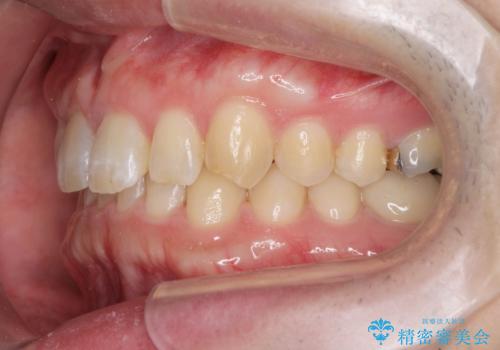

ディープバイトのマウスピース矯正

- 飛び出してしまい、隙間のある前歯をきれいに並べたい、と矯正治療を希望され来院されました。

上顎前歯を後方に引き、隙間を閉じるためには下顎前歯の絶対的な圧下を行い、深い噛み合わせを改善することが必要です。

圧下は歯の動きの中でも難しい動きの一つで時間がかかることが多いです。

前歯でチューイーをしっかり噛み、咬合圧を伝えたことで下顎前歯が圧下し、上顎前歯の隙間を閉じることができました。